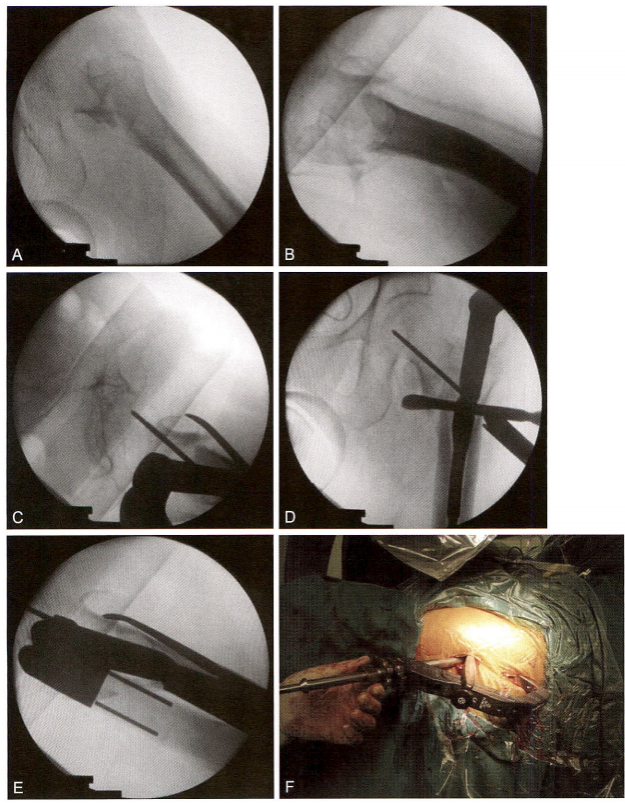

4)术中复位技巧4:对于难复型病例,可以综合运用多种方法复位, 此类简单骨折(AO 分型A1.2, 即2007版的A1.3) 复位非常困难。往往 由于复位不良,导致手术失败(图9-11A 、B); 牵引后正位复位不良, 近端矢状位旋前(图9-11C); 牵引后侧位复位不良,近端向前移位(图 9-11D) 。用点状复位钳钳夹复位,正、侧位良好,并用克氏针临时固定, 然后常规髓内钉导针定位(图9-11E、F)。复位之后,需采用复位质量标准进行评价(表9-3、表9-4)。在开口 之前,不可接受的复位需要继续调整。

图9-11 难复型病例。A 、B.术前CT;C. 牵引后正位示复位不良,近端矢状位旋前;

D. 牵引后侧位复位不良,近端向前移位;E 、F. 采用多种复位方法后